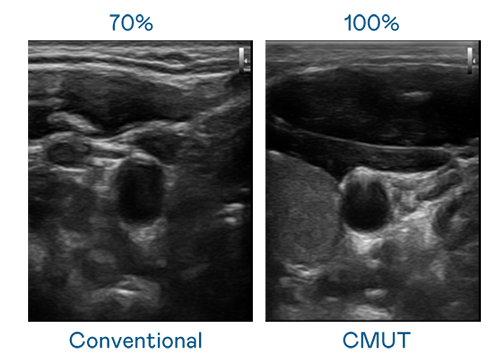

CMUT 技術是一種用電容式微機電元件來產生超音波訊號的技術。與傳統 PZT 壓電式技術相比,CMUT 頻寬增加 30%,更寬頻的超音波訊號讓影像解析度大幅提升,是實現高影像品質醫療超音波掃描、促進精準醫療發展的關鍵技術。

超音波影像的解析度高低,首先取決於探頭能發出的訊號頻寬。金年会 CMUT 可提供高清晰的超音波訊號,提供高頻寬、高靈敏度、影像紋理細節更高的超音波影像,協助醫護人員縮短影像判讀時間及利用精準的醫療影像進行診斷。